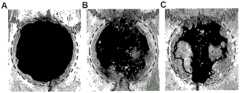

FIG. 4 is the result of Micro-CT 3D reconstruction of hydrogel in vivo bone defect repair experiment, wherein A is a control group, B is a hydrogel group, and C is a hydrogel group containing rhNMP-2.

The test method and conditions were: 15 SD male rats (250-300g) were randomly divided into 3 groups, namely a blank control group, a hydrogel repair group, and a hydrogel repair group containing rhBMP-2 (containing 300. mu.g of rhBMP-2), and 5 rats were each group. 0.1ml of new injection of 50% fast dormancy anesthetizes the rat, prepares skin, and 75% alcohol is disinfected, makes a sagittal incision at the top of the head, opens the full-layer mucoperiosteum flap, uses the bone drill of the department of plantation to make a circular defect with a diameter of 8mm, and the drill grinds the in-process and constantly washes with normal saline, prevents to rub the themogenesis and lead to the necrosis of local tissue. After implantation of 8w of material, rats were subjected to heart perfusion under anesthesia (10% neutral formalin), the calvaria bone was removed, the specimen was fixed in 10% neutral formalin, and Micro-CT scanning and 3D reconstruction were performed on the specimen.

As shown in FIG. 4, it can be seen that the defect of the control group had a part of new bone formation at the edge, most of the defect was not repaired, the hydrogel group had a small amount of new bone formation at the middle of the defect in addition to the new bone formation at the edge of the defect, and the hydrogel repair group containing rhBMP-2 had a large amount of new bone formation at the middle of the defect, which was significantly greater than that of the other two groups.